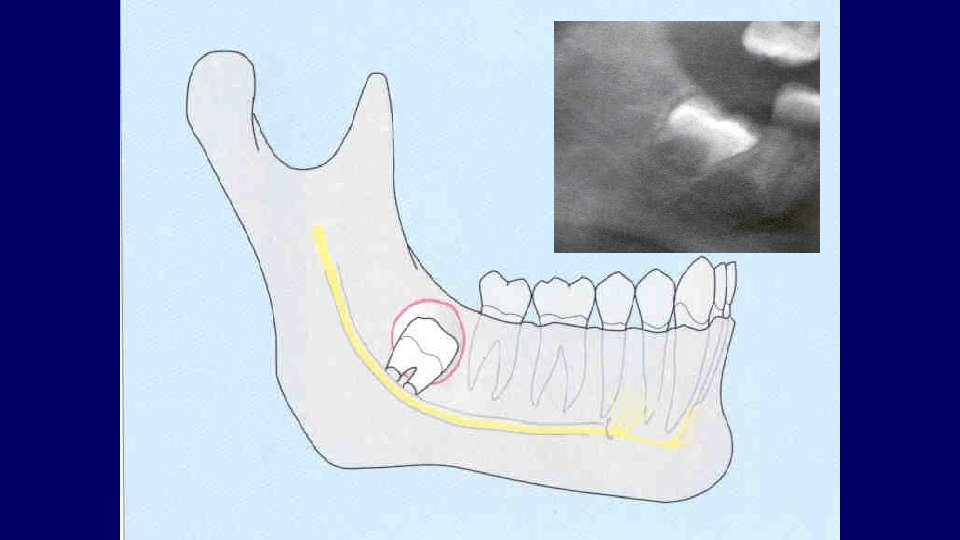

Types of impaction • Vertical • Mesioangular • Distoangular • Horizontal • Transverse

(2) Depth of impaction

Pell & Gregory Classification • Based on the amount of tooth covered by the anterior border of the ramus • The depth of the impaction relative to the adjacent tooth

Pell & Gregory • Depth of Impaction – Mandibular Class A Class B Class C

Pell & Gregory